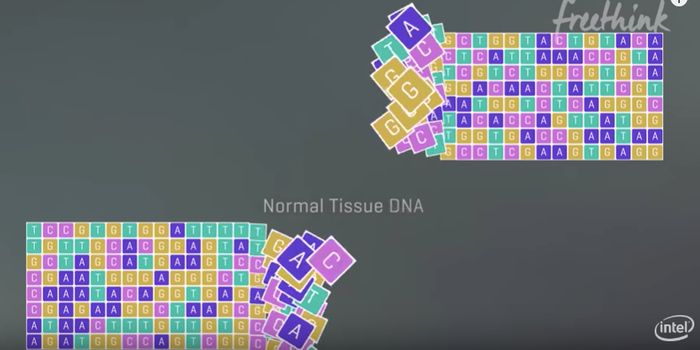

FEB 21, 2020Clinical & Molecular DXDiagnosing coronavirus is done through next-generation sequencing, real-time RT-PCR tests, cell culture, and electron mi ...